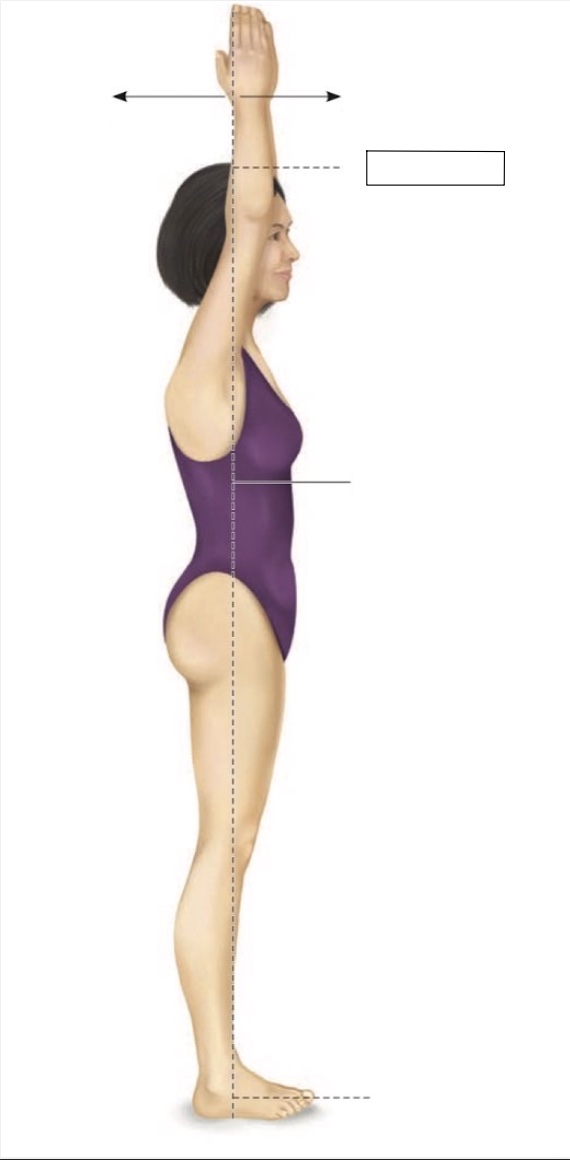

Superior

Midline

Midaxillary

Torso